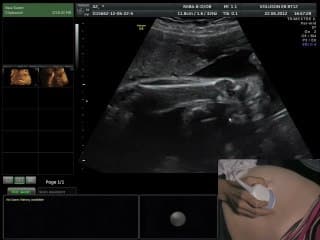

La plus grande ressource vidéo en échographie fœtale de France. Conférences, cours magistraux, démonstrations pratiques et podcasts par les experts du Collège Français d'Échographie Fœtale.

La médiathèque du Collège Français d'Échographie Fœtale (CFEF) constitue l'une des plus importantes collections de ressources vidéo dédiées à l'échographie fœtale en France. Avec plus de 3 261 vidéos, elle couvre l'ensemble des thématiques liées à la pratique échographique prénatale.

Vous y trouverez des conférences présentées lors des congrès nationaux et internationaux, des cours magistraux dispensés par des experts reconnus, des démonstrations pratiques sur des cas cliniques réels, ainsi que des podcasts et tables rondes sur les dernières avancées de la spécialité.